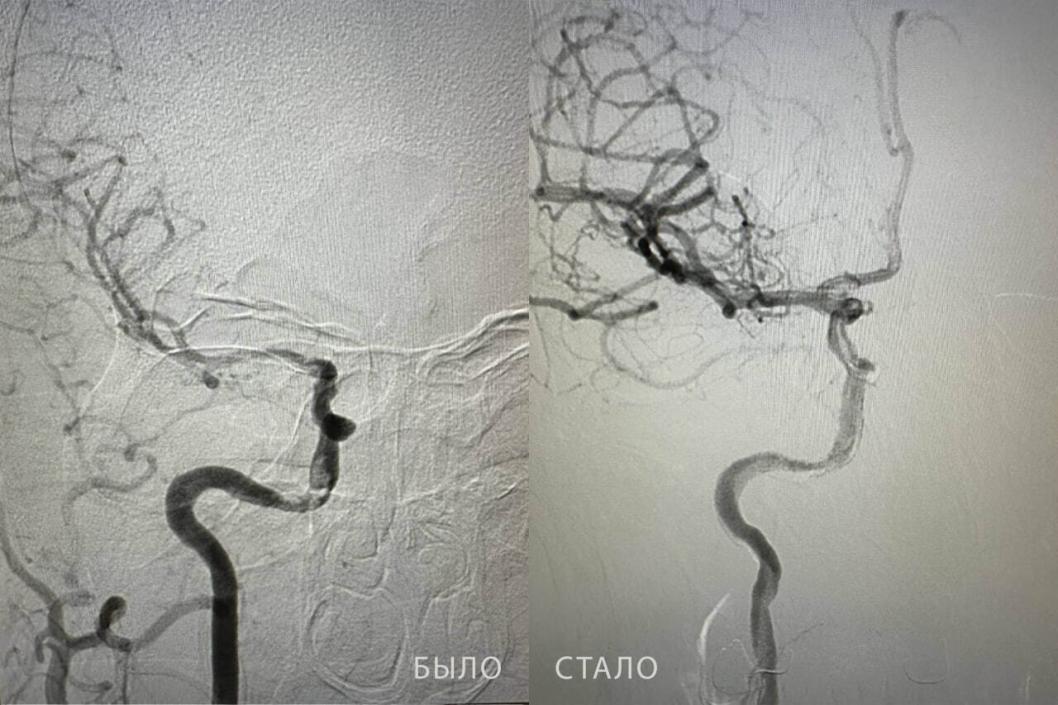

Сразу после поступления пациента осмотрел врач‑невролог Жахонбек Латипов. Детальная диагностика выявила опасную патологию: тромб в правой внутренней сонной артерии. Ситуация требовала немедленного вмешательства, потому что промедление могло привести к необратимым последствиям.

Операцию провел ангиохирург Бакназар Абдыкадыров. Более получаса доктор кропотливо работал, чтобы извлечь тромб длиной около двух сантиметров. Успешное завершение операции позволило полностью восстановить кровоток в сосуде.